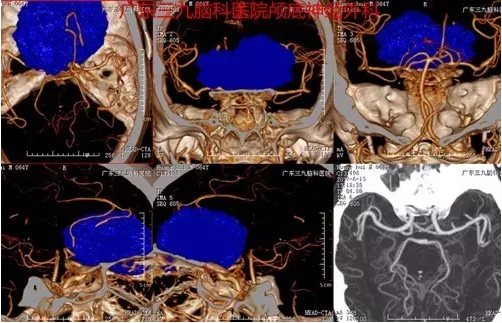

图3:术前CTA提示肿瘤血供极丰富

本例患者为老年男性,病程长,以头晕头痛就诊,伴恶心呕吐,未有明确定位症状,易误诊,行头颅CT及MR检查提示前颅窝底脑膜瘤。临床辅助检查中,头颅MR扫描对前颅窝底脑膜瘤的诊断意义最大。MRI 检查不仅可以显示肿瘤的体积及具体起源部位,而且还可以清楚显示肿瘤与邻近重要结构,如视神经、颈内动脉及其分支、垂体柄、下丘脑等的关系,这对指导手术人路的选择具有重要的意义。多数情况下前颅窝底脑膜瘤的MR增强扫描可见较均匀一致的强化,这与脑膜瘤的血运较丰富有关,有的情况下,如果肿瘤增强十分明显,而且肿瘤瘤内或周边有较多的血管流空,多提示肿瘤的供血血管较多,肿瘤血运丰富。本例患者术前CTA提示其内血供丰富,双侧大脑前动脉受压明显向右侧偏移,MR增强明显,其内见较多流空影,大小约5.9×6.3×3.5cm,体积巨大,且与嗅沟、视神经、垂体炳、下丘脑等关系密切,手术难度较大,术中行冠状切口经额予以全切除,切除时间约半小时,术中出血少,术后患者恢复快,术后严格监测血离子、尿量、垂体激素等的变化,术后患者出现一过性精神症状,目前恢复良好出院。